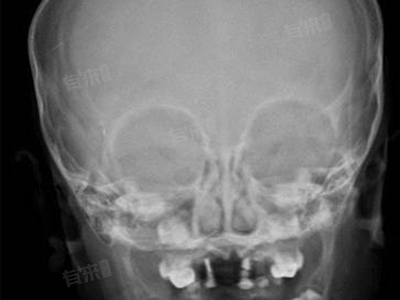

- 头颅CT或MRI检查:头颅CT或MRI是评估头顶凹陷的首选影像学检查方法,它们能够清晰地显示颅骨的结构和脑组织的状况,有助于判断凹陷是否由颅骨骨折、颅骨缺损或脑组织病变引起。

- 病史询问与体格检查:详细询问患者的病史,包括既往的头部外伤史、手术史以及家族遗传病史等,有助于医生更全面地了解病情。同时,进行体格检查,观察凹陷的形状、大小、深度以及周围组织的状况。